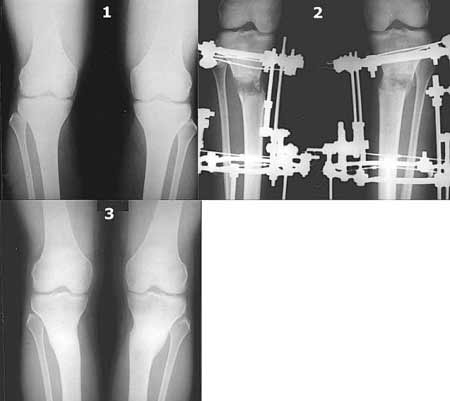

Картинки - в приложении.Будут вопросы - готов ответить.

Ещё картинка - схема. Хотя у Соломина всё написано.

Вот ещё картинки, которые отправлял в Ортопод. Коррекция кривизны и удлинение на 3 см.

I do upper tibial osteotomies with either an ilizarov fixator and acute correction of the deformity or with an orthofix with gradual correction.

Sending you pics of the steps of the osteotomy and the frame.

You can do the osteotomy in a "focal dome" or in a transverse fashion. The dome has the advantage of having a good contact, allowing weight bearing as tolerated early on.

The level is below the tibial tuberosity.

The frame I use is pretty simple, with one wire each in the proximal and distal ring, two schanz pins in the proximal ring, and one each in the middle and distal ring.

I preconstruct a frame with the proximal ring in varus by the use of coupled washers in the threaded rods in the front and back. These are used as hinges, and after the correction, a medial and lateral threaded rod is also added.

Since the center of rotation of these deformities is usually near the knee joint line, lateral translation of the distal fragment is necessary to normalise all the axes.

You can also do the osteotomy in a transverse fashion.

When I use an orthofix fixator, the osteotomy is oblique, starting below the tuberosity and ending 1 cm away from the lateral cortex at the level of the head of the fibula. No fibular osteotomy is needed there. The deformity is gradually corrected over 2 or three weeks.

You could also do the same with an ilizarov fixator